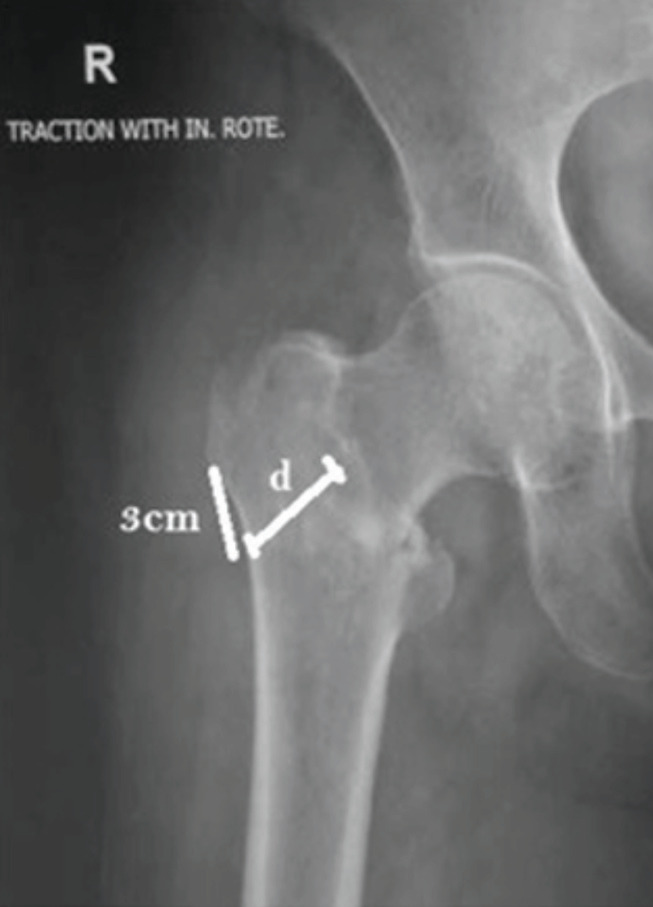

Introduction: The Intertrochanteric fracture is a common hip trauma encountered in elderly patients. There is a lack of general agreement regarding its surgical management and choice of implant. Purpose of this study to conclude the final decision matrix regarding surgical management of intertrochanteric fractures based on parameters assessed on plain radiographs and CT scan.

Materials and methods: We have retrospectively evaluated 55 patients with intertrochanteric fractures presented to our institute after informed consent with radiographs and CT scans between July 2017 to July 2018. Assessment of various parameters regarding fracture geometry and classification as well as measurement was done.

Results: Mean lateral wall thickness in present study was 20.76mm. Incidence of coronal fragments was 90.9% and absence of coronal fragment in 5 patients. We noted the cases with anterior comminution had also a posterior comminution rendered the fracture unstable in almost 20 % cases.

Conclusion: Better understanding of fracture geometry by combined used of radiograph and CT scan enhanced preoperative planning, choice of suitable implant, helps in reduction manoeuvre and improving quality of osteosynthesis.